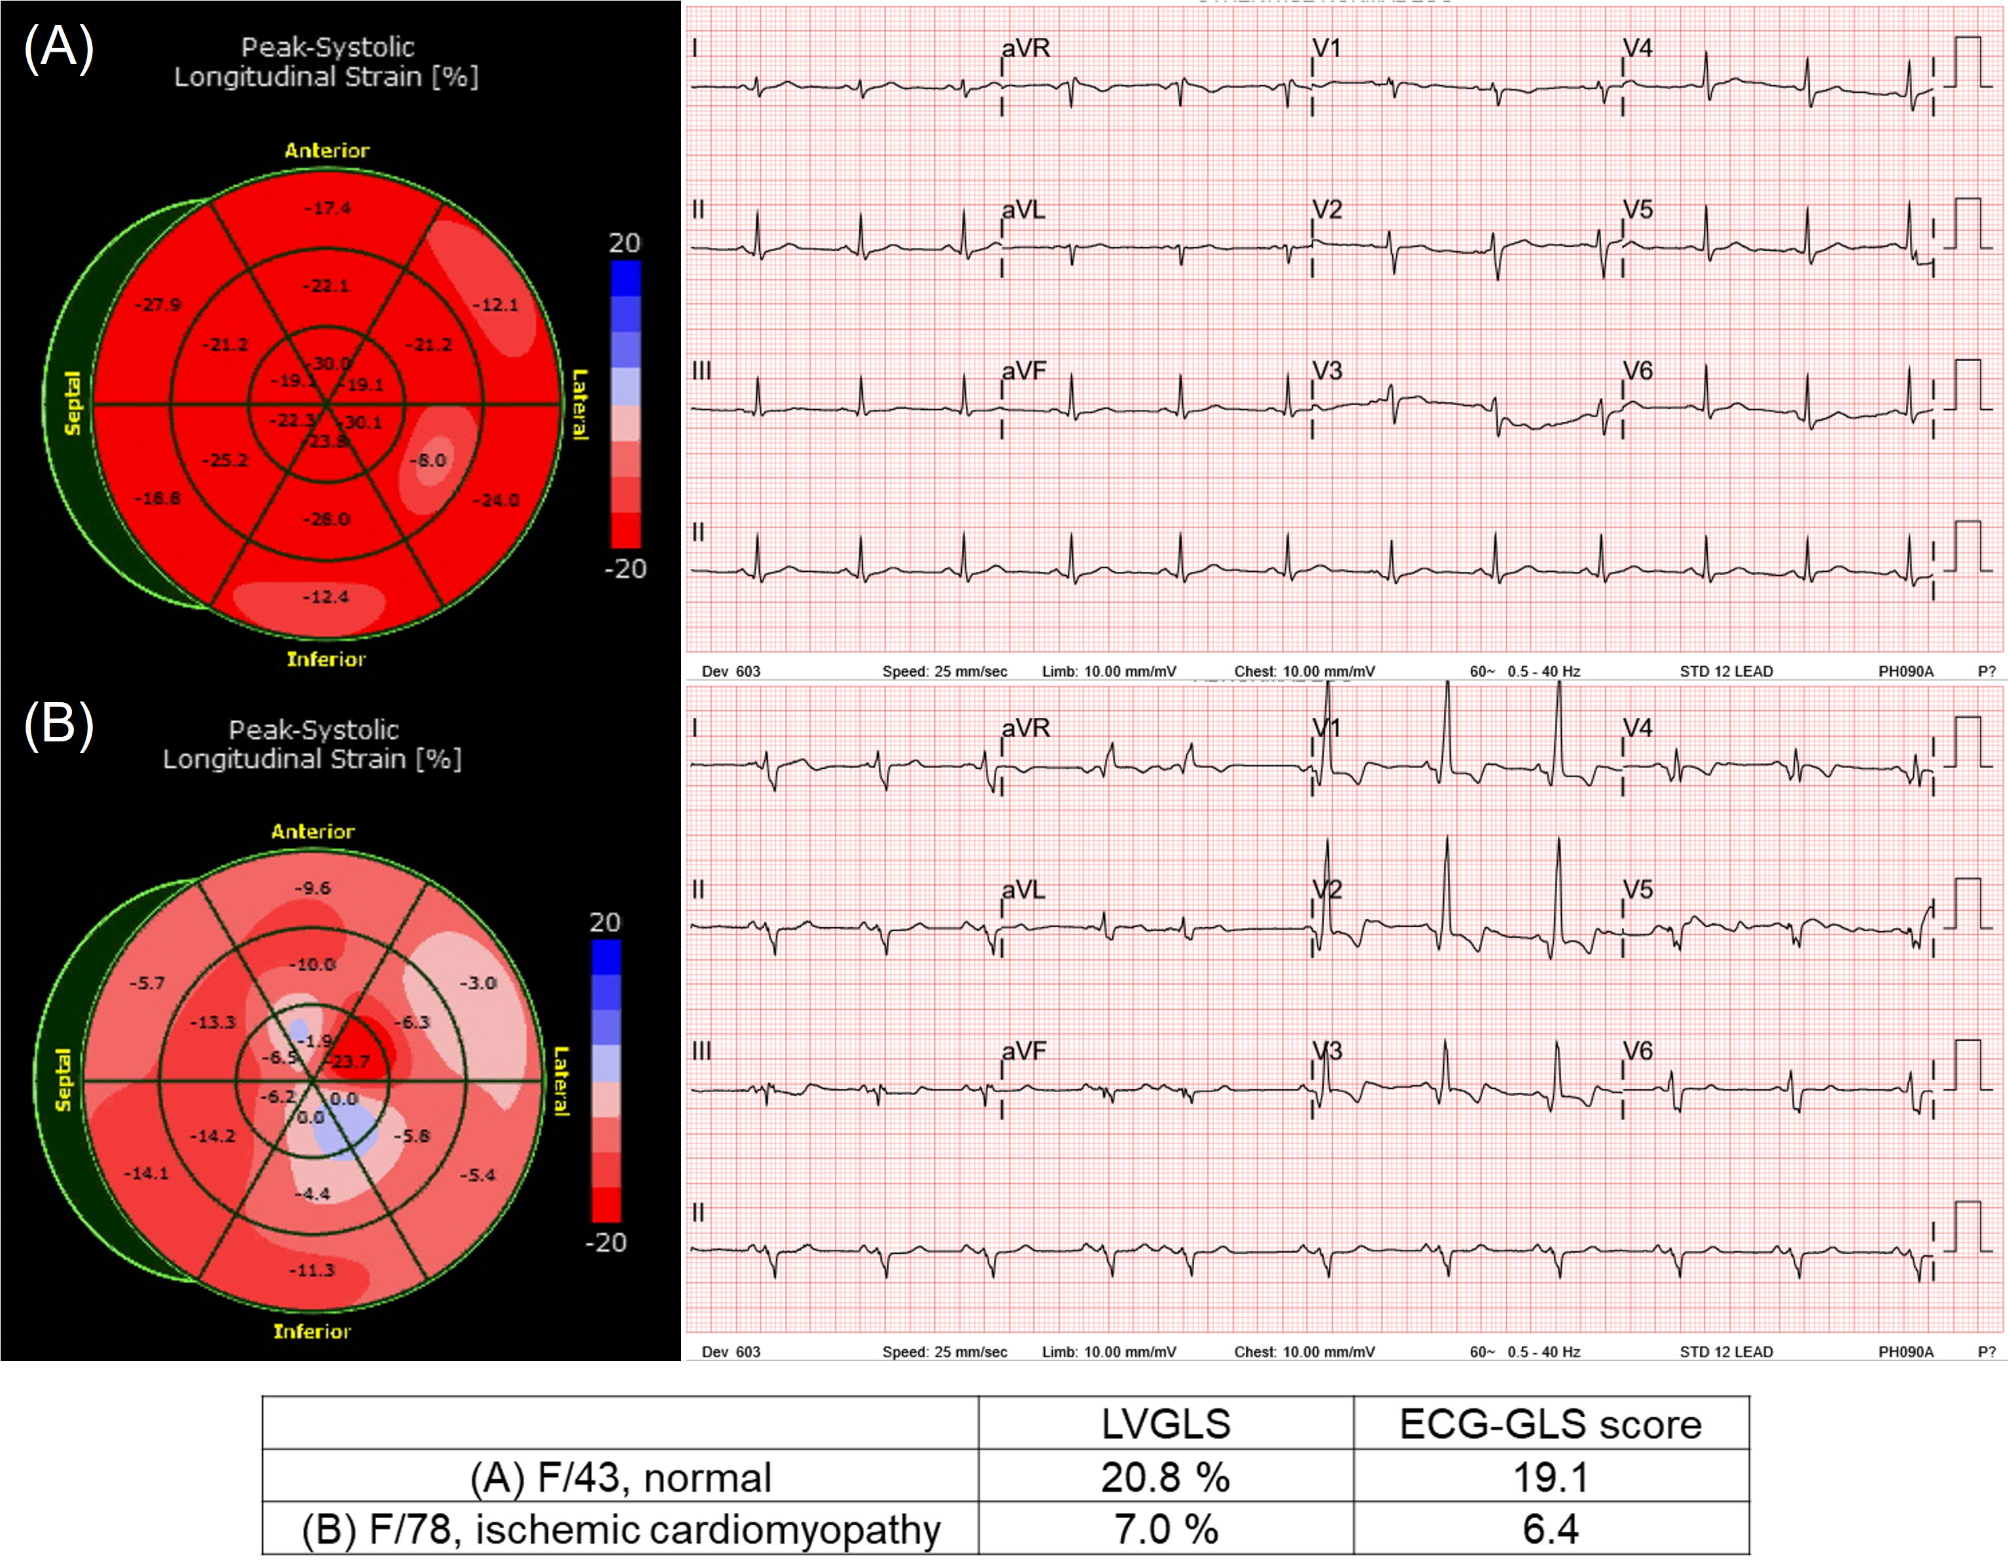

Fig. 2

Representative case of LVGLS and ECG-GLS score pair. (A) A 43-year-old female who underwent echocardiography for routine checkup. (B) A 78-year-old female with ischemic cardiomyopathy.